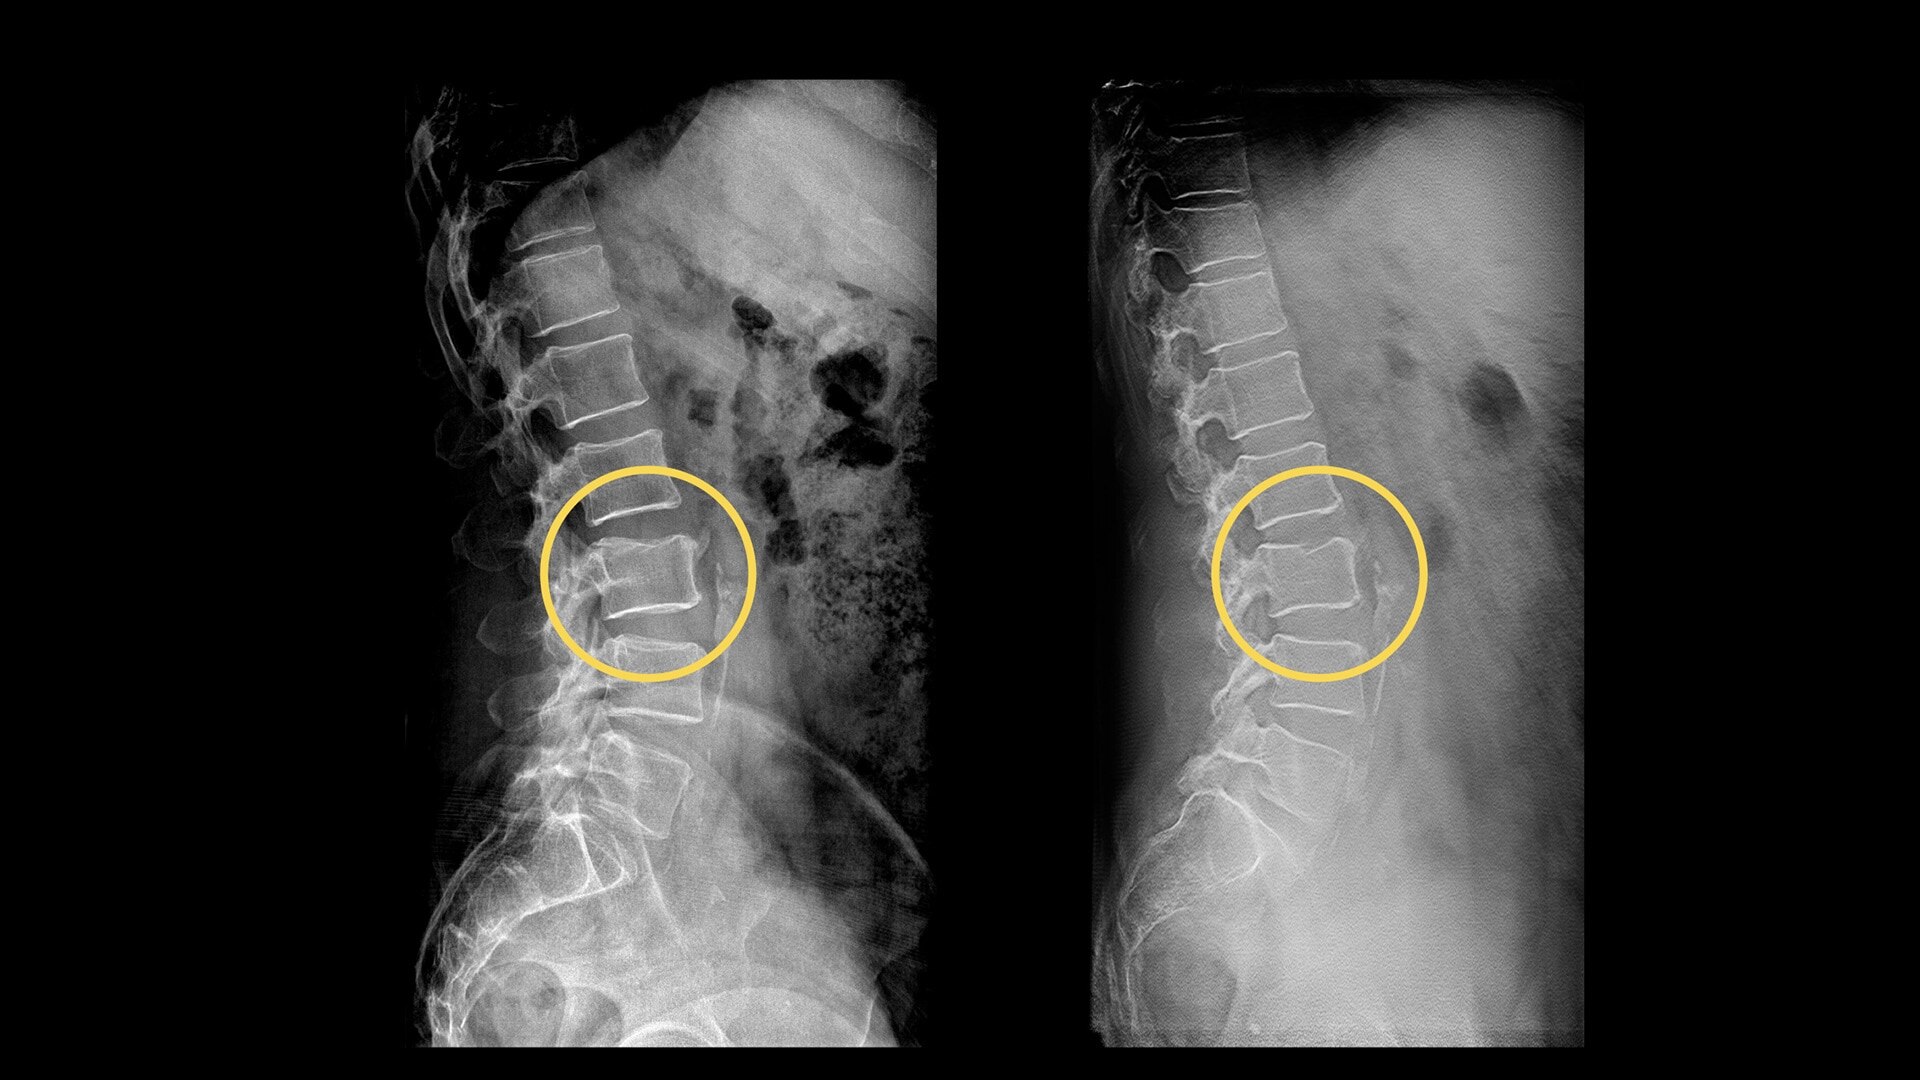

Your department relies on standard radiography as the first diagnostic test for most chest, orthopedic and trauma cases. But hairline fractures or non-displaced fractures are difficult to detect on conventional X-rays.13 According to a recent study, 33% of scaphoid fractures are missed on the first X-ray.14

Digital tomosynthesis can help you reduce time-to-diagnosis, decrease department costs and improve patient outcomes.

13. P. M. Parizel et al. "Trauma of the spine and spinal cord: Imaging strategies." Eur Spine J. 2010 Mar; 19(Suppl 1): 8–17.